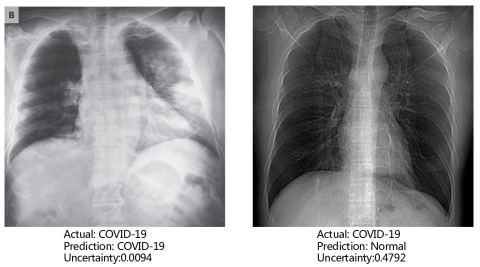

Uncertainty Estimation: One remarkable advantage of our model is the ability to quantify the uncertainty in the final prediction, which is significantly crucial for COVID-19 detection. This is done by obtaining the variance in the output of different experts in MUL as described in Section III-C. The larger the variance is, the more different experts disagree with each other, and, hence, the more uncertain the model is about the final prediction. We present two CXR samples in Fig. 6, including the predictions and the corresponding uncertainty level by RCoNet. We can see that the correctly classified CXR image has a low uncertainty level about its prediction, i.e., 0.0094, and the misclassified CXR sample with a high uncertainty level, i.e., 0.4792, suggests that an alternative way of diagnosis should be sought to correct this prediction. This greatly improves the reliability of the prediction by RCoNet, and reduces the chance of misdiagnosis. We also show in Fig. 7 the average uncertainty levels of RCoNet trained on clean and noisy datasets with different ratios of noisy samples. It can be observed that the uncertainty level increases almost linearly with the percentage of noisy samples in the dataset, which highlights the negative impact of noise on model training.